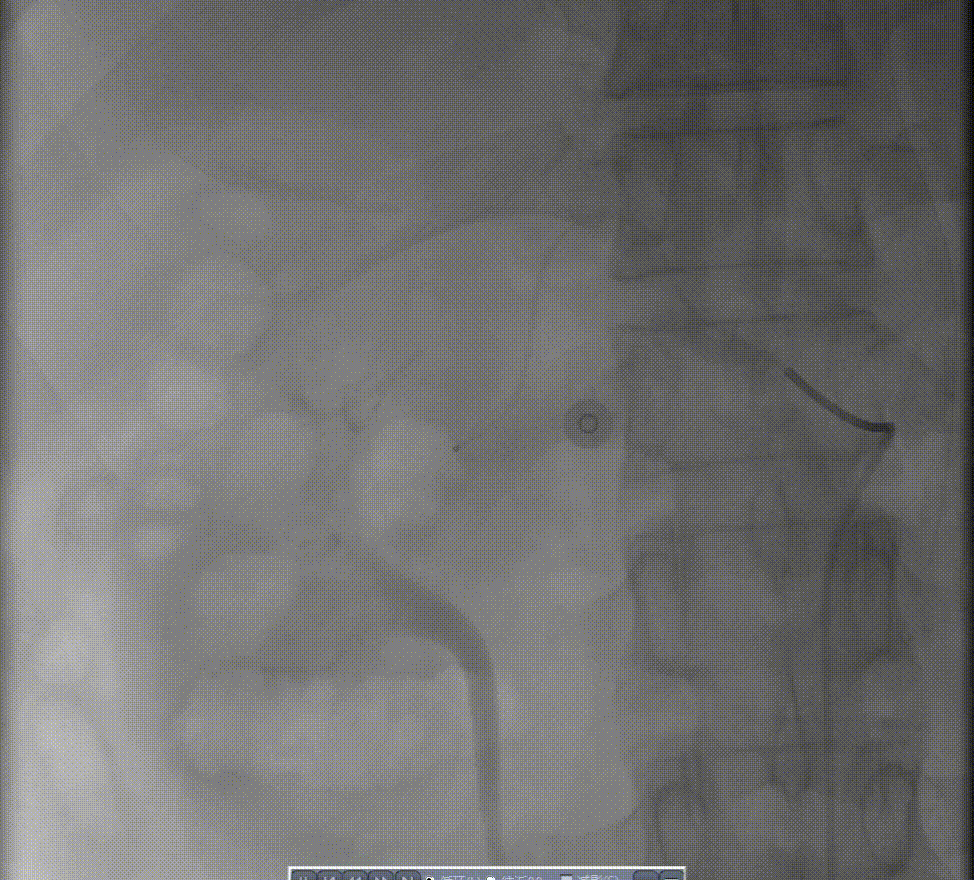

图:造影见胃十二指肠动脉近段动脉瘤,并可见造影剂溢出;弹簧圈栓塞后动脉瘤闭塞。